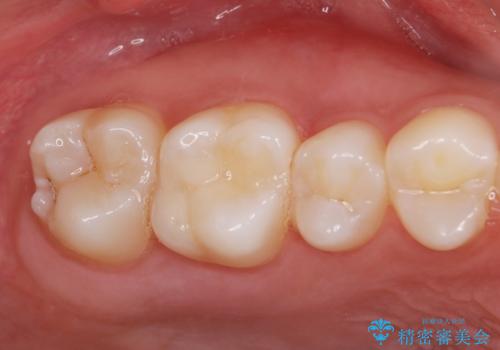

[ 歯並びと虫歯治療 ] 矯正治療とセラミック治療の包括治療

![[ 歯並びと虫歯治療 ] 矯正治療とセラミック治療の包括治療の症例 治療後](https://seimitsushinbi.jp/wp/wp-content/uploads/2023/12/d2649953cbde2ed7237dd47483ac69db-1-500x350.jpg?v=1703058723)